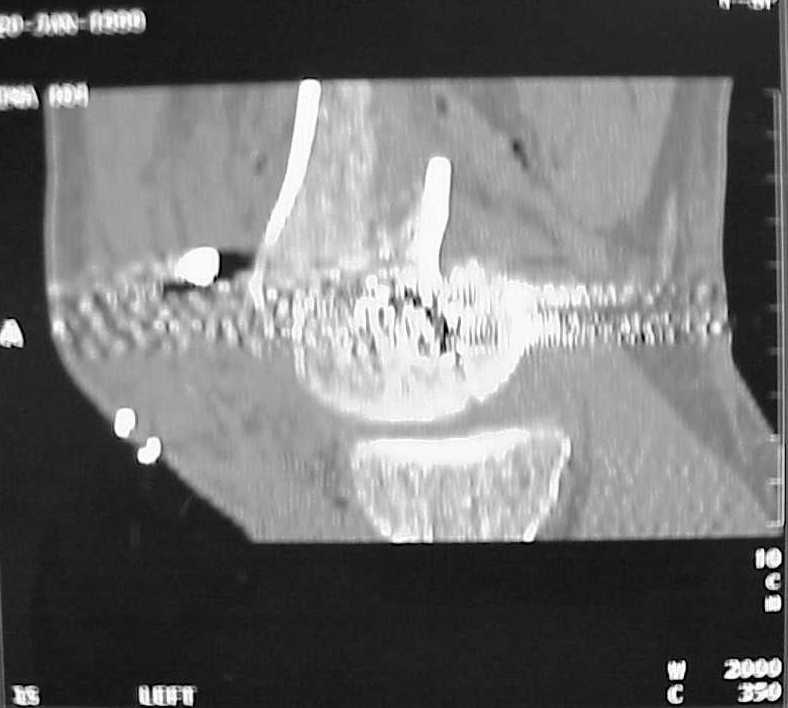

Мы пошли на операцию с планом попытаться сделать закрытый интрамедулярный, а не получится - сделать аппаратом. Посчитали, что получилось, хотя на еженедельной конференции ожидаются некоторые проблемы с объяснениями ;-)

Насчет стабильности для ранней нагрузки, конечно, сомнительно, но при таком повреждении ранняя нагрузка противопоказана в любом случае. Для ранних движений Должно хватить. Снимки в следующем сообщении.

воспользовались для репозиции, см. приложение.

Да, примерно так и сделали. Надо было, пожалуй, кончик гвоздя еще спилить, чтобы отверстие было еще дистальнее. Англоязычные коллеги еще

советовали винты в передне-заднем направлении вводить, но что-то не увидел, где там подходящее место.